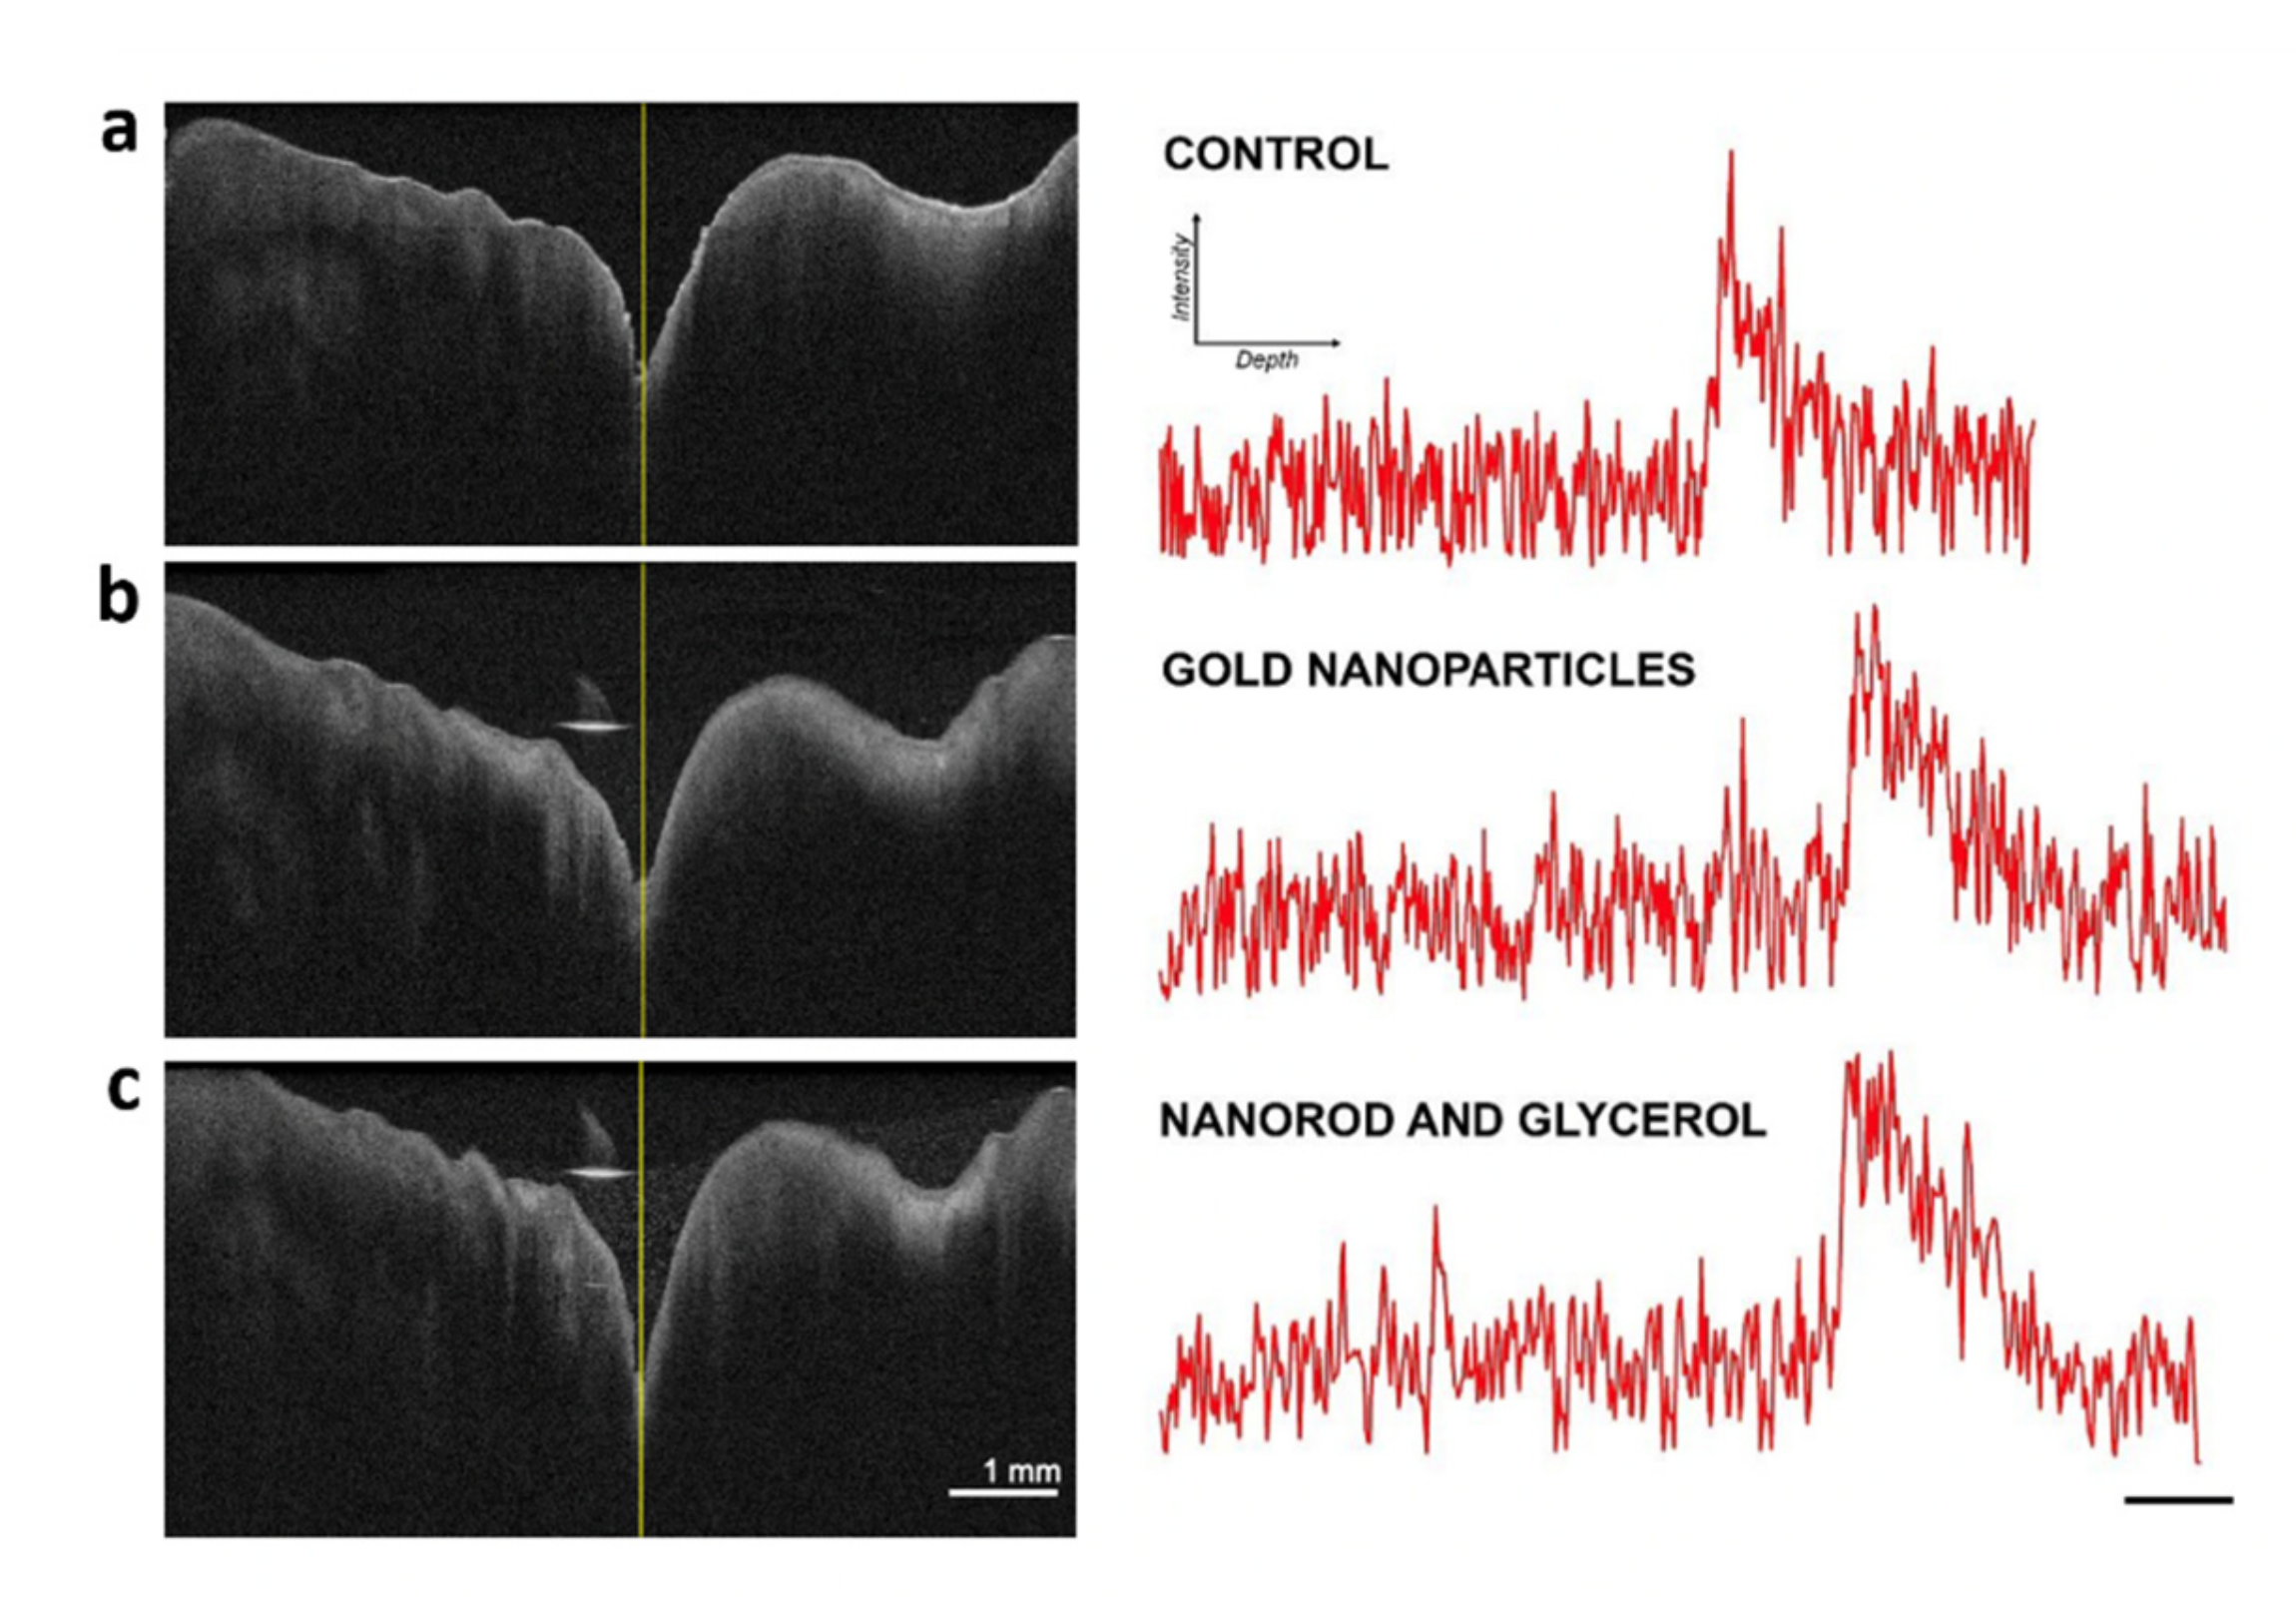

- Braz, A.; de Araujo, R.; Ohulchanskyy, T.; Shukla, S.; Bergey, E.; Gomes, A.; Prasad, P. In Situ Gold Nanoparticles Formation: Contrast Agent for Dental Optical Coherence Tomography. J. Biomed. Opt. 2012, 17, 066003. [Google Scholar] [CrossRef] [PubMed]